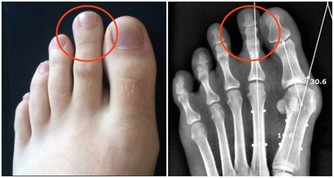

血管阻塞是長年累月的結果,最初發生問題的「徵兆」是什麼呢?腳是人體的末梢,也是心臟最遠端,血管有問題,腳最先有感覺。

因此血管阻塞的最初有兩個症狀,一是腿開始怕冷,二是走較久的路時,只有一邊的腿容易疲勞酸痛。

此外,還有個比較明確的信號可以驗證:人的手腕上能摸到脈搏,其實,人的足部足背正中最高點,輕輕摸,能感受到脈動。

平時能摸到這個足部的脈搏,證明我們的動脈血一直通到了足背部。可當走一段距離之後,再摸,反而摸不到這個脈搏,此時,就可能發生了輕度的動脈血管阻塞。